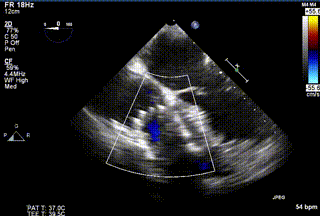

患者一术前心超

患者一术后心超